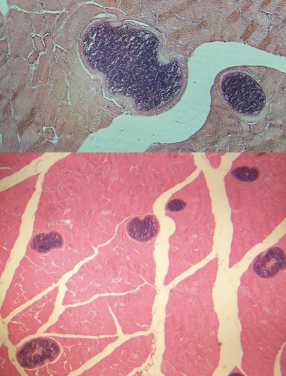

Sarcocystis cysts